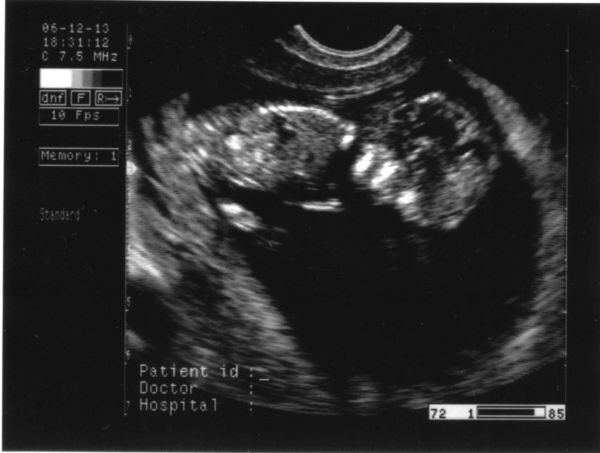

Ha nem baj, én is feltenném a 12. heti UH-n készült képet (12+4 itt). Sajna nem lett a legjobb, pedig olyan jó képeket lehetett volna a vizsgálat elején csinálni, de aztán mire a doki fotózgatni kezdett, Kisborsó elfordult, és ezt sikerült… Persze a végén magyarázatot kértünk, és amikor magyarázott, hogy mi micsoda nyitva maradt a tolla, úgyhogy a tollvonások azok a képen a dokitól származnak…

De nem baj, így is nagyon édi Kisborsó